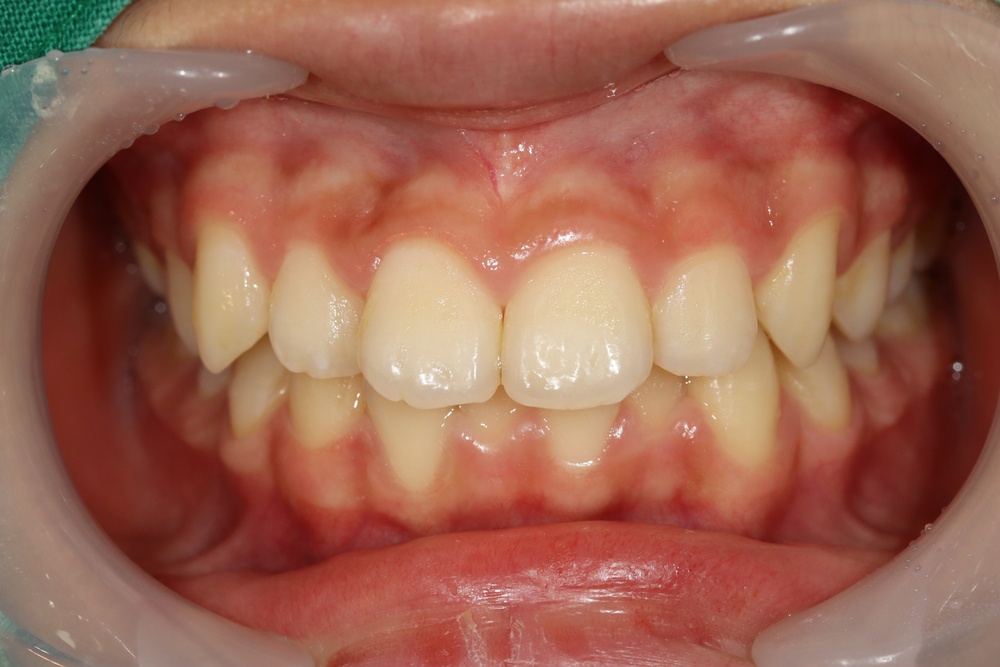

거꾸로 물려요(반대교합), 아래턱이 나왔어요(주걱턱)으로 온 친구입니다.

치료기간을 최소화하려면 이가 좀 더 난 뒤에 시작하는 것이 좋아서, 6개월 정도 기다린 후 페이스마스크와 브라켓 장치료 치료를 시작하였습니다.

중안모의 볼륨이 살아나서 옆모습이 좋아졌고, 이도 가지런해졌습니다.

반대교합이 개선되면 밥먹기 편해지는 걸 아이들도 느끼는 경우가 많은데, 이 친구도 그랬습니다.